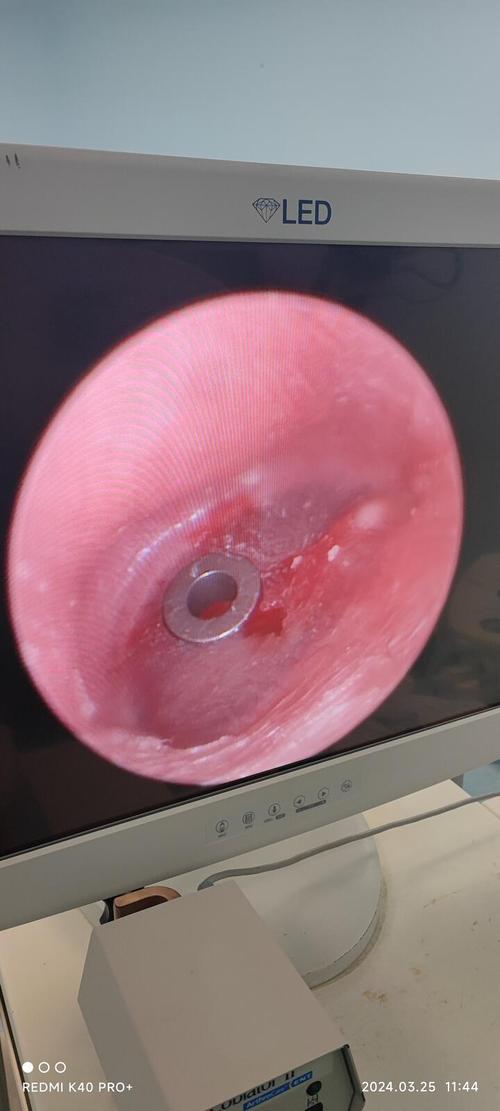

- 方式: 医生会使用一个叫做耳内镜的细长、带摄像头和光源的仪器,轻轻伸入孩子的外耳道。

- 图示: 耳内镜能将鼓膜的放大图像实时显示在屏幕上,让医生看得非常清楚。

置入通气管

- 方式: 医生会用一个细小的器械,将一个预先准备好的通气管(也叫“鼓膜通气管”或“Grommet”)放入鼓膜的小切口中。

- 图示: 通气管放置好后,会像一个小塞子一样固定在鼓膜上,一端在中耳内,一端在外耳道。

手术完成

- 方式: 通气管放置到位后,医生会退出耳内镜,手术结束。

- 图示: 手术完成后,鼓膜上的通气管清晰可见,它允许空气和液体自由通过,从而解决中耳问题。